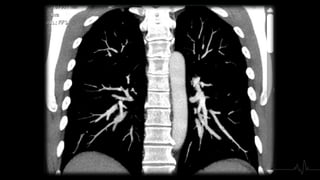

TÉCNICA - ANGIOTAC

• Contraste: 50 ml a un flujo de 4 ml/sg y lavado posterior con 30 ml de

suero salino

• Kilovoltaje se decide en función del peso del paciente: 80 kV hasta 70

Kg, 100 kV entre 70-100 Kg y 120 kV por encima de 100 Kg.

• Se dispara con un retardo de 6 seg, con técnica de bolus tracking,

posicionando el (ROI) en la arteria pulmonar, a 100 (UH).

• Adquisición se realiza con la respiración suspendida, pero no tras

inspiración profunda para evitar la dilución del contraste en la aurícula

derecha.

TÉCNICA - ANGIOTAC •Contraste: 50 ml a un flujo de 4 ml/sg y lavado posterior con 30 ml de suero salino • Kilovoltaje se decide en función del peso del paciente: 80 kV hasta 70 Kg, 100 kV entre 70-100 Kg y 120 kV por encima de 100 Kg. • Se dispara con un retardo de 6 seg, con técnica de bolus tracking, posicionando el (ROI) en la arteria pulmonar, a 100 (UH). • Adquisición se realiza con la respiración suspendida, pero no tras inspiración profunda para evitar la dilución del contraste en la aurícula derecha.